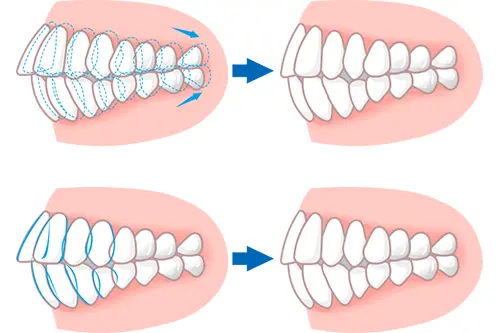

歯を動かすスペースが確保できる

八重歯を列に戻すためには、その歯が入るための隙間が必要です。奥歯を後方へ移動させることでスペースを作れる場合や、歯列のアーチを横に広げることで隙間が確保できる場合は、マウスピース矯正が非常に適しています。

特にマウスピース矯正は、奥歯を後ろに送る動きが得意とされています。親知らずを抜歯してスペースを作り、全体的に歯を後ろに下げることで、前歯のガタツキを解消できるケースは、マウスピース矯正の良い適応例といえます。

歯のスペースの作り方